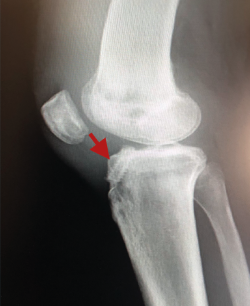

El tratamiento de un paciente que sufre una rotura aguda del LCA (Figura 2) sigue siendo motivo de discusión(9). Hay muchos condicionantes que influyen en el manejo terapéutico de estas lesiones (ya sea quirúrgico como no quirúrgico), como son la edad, la ocupación, la actividad deportiva, las lesiones asociadas, el grado de laxitud de la rodilla, las expectativas o las recidivas de la lesión, entre otras. El riesgo de artrosis tras la rotura aguda del LCA será mayor en ambos grupos con respecto a la población sana, sea cual sea el tratamiento(12). Los factores de riesgo más importantes para el desarrollo de artropatía son: lesión meniscal, meniscectomía e injerto hueso-tendón-hueso (HTH).

Un diagnóstico y una planificación correctos son fundamentales. En caso de rotura de plastia del LCA (Figura 3), se hace obligatoria, además de una detallada exploración, un correcto estudio radiológico completo que incluya radiología convencional y resonancia magnética (RM) –estudio de lesiones acompañantes o degeneración previa–. En ocasiones en donde la anamnesis/exploración lo justifique, pueden ser también necesarias telemetrías de extremidades inferiores, radiología forzadas (si existiera inestabilidad mediolateral) o tomografía axial computarizada (TAC) –valoración de la posición y la calidad de los túneles–.